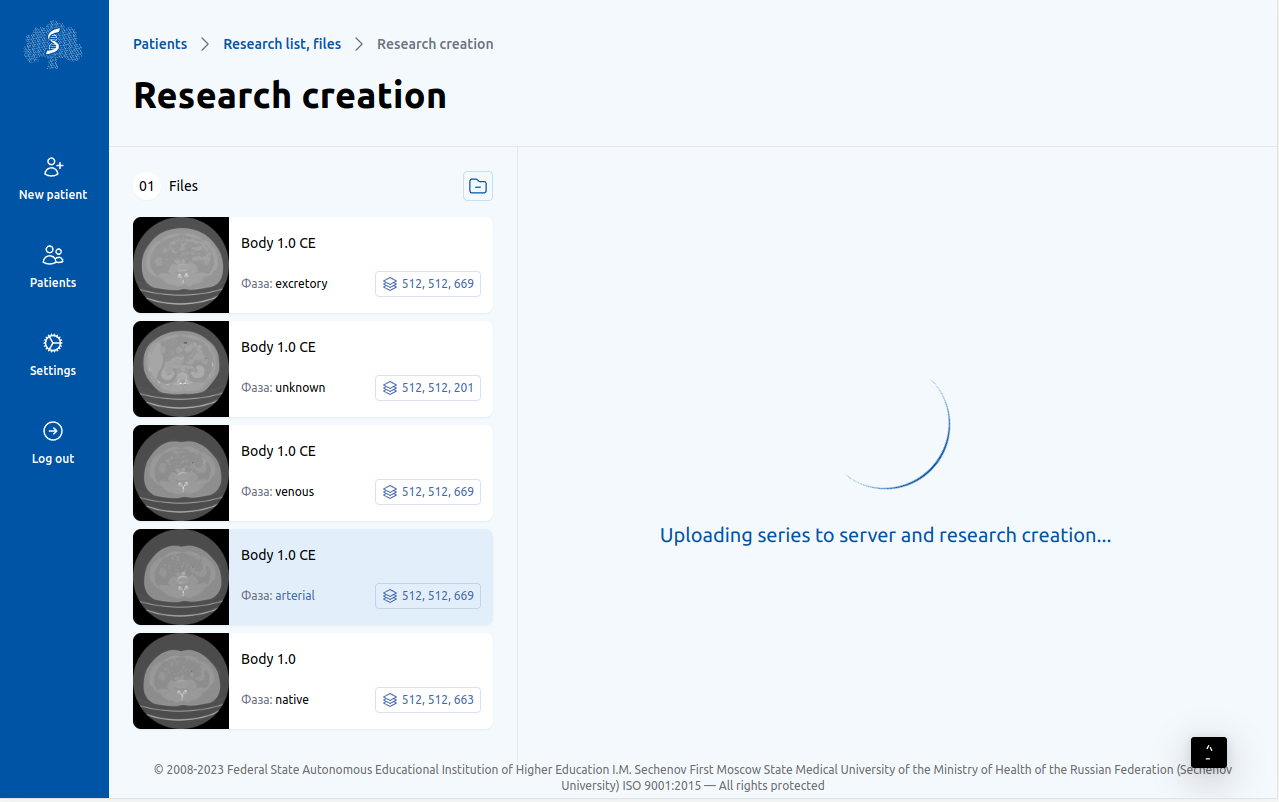

3

Отправка на сервер

Сервис выделяет анатомические структуры в течение нескольких минут